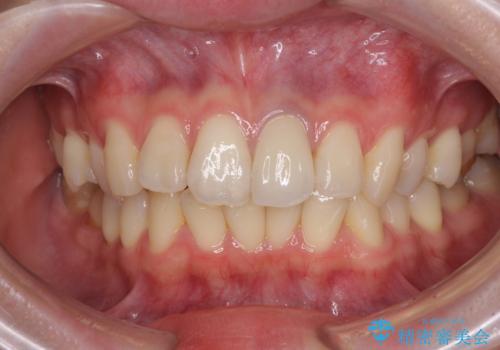

境目が見えている前歯のクラウンをオールセラミッククラウンに

- 前歯のクラウン付近の歯肉が黒く見えることを気にして来院された患者様です。

根管治療を行った後に、オールセラミッククラウンにて補綴することとしました。

オーダーメイドタイプのクラウンを選択いただいたので、まるで天然の歯と見間違うほど自然に仕上がり、患者様には大変満足していただきました。